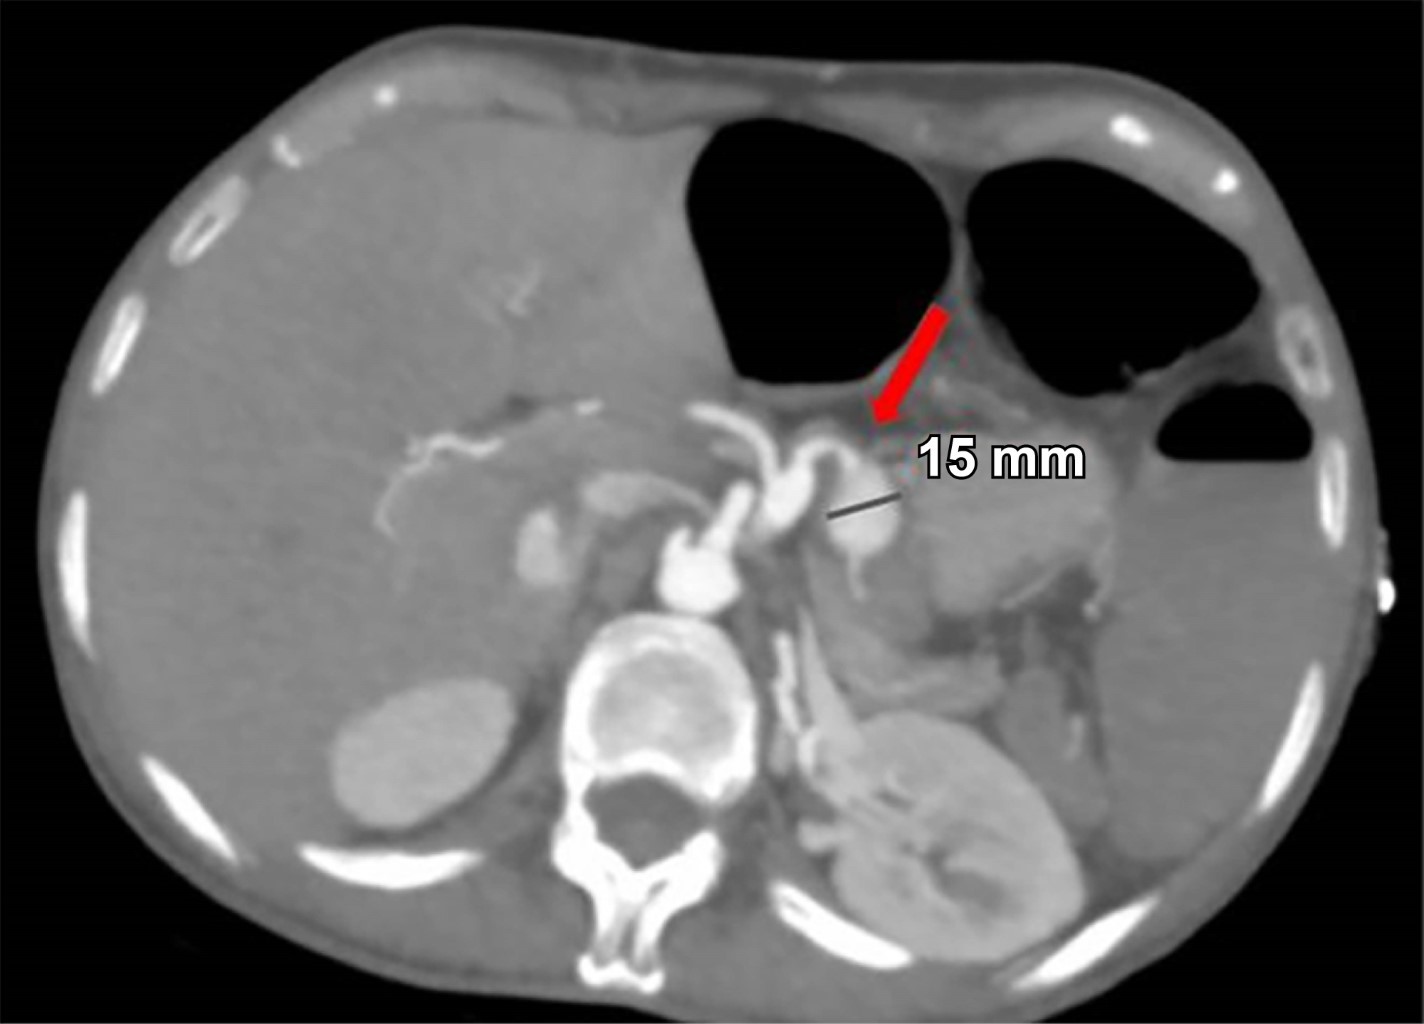

Mujer de 44 años quien 6 meses previos a su ingreso refiere disminución progresiva de la clase funcional debido a un soplo aórtico, por lo que se realizó cambio valvular con la necesidad de ser sometida a circulación extracorpórea y uso de vasopresores. Durante los primeros 10 días postquirúrgicos se diagnostica obstrucción intestinal, por lo que se realiza TC con hallazgo incidental de arteria esplénica (Figura 1) con dilatación aneurismática de hasta 12 mm, en un nuevo estudio de TC a las 24 horas (Figura 2) con ligero aumento del diámetro de aneurisma esplénico hasta 15 mm, pasadas 96 horas solicita nueva TC (Figura 3) y se evidencia mejor definición de la dilatación aneurismática de la arteria esplénica con diámetro actual de 15 mm (previamente de 12 mm). Con los hallazgos tomográficos previamente descritos, se pudo observar la evolución del proceso de dilatación aneurismática con ruptura contenida por el parénquima pancreático, la paciente cursó con un cuadro de obstrucción intestinal con desimpactación endoscópica y dolor abdominal, por lo que seguramente se enmascaró el cuadro clínico.

Figura 1